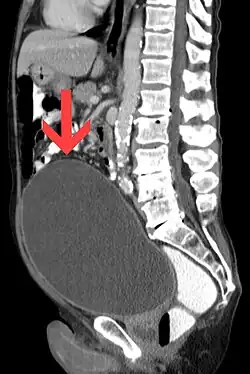

Harnverhalt mit riesiger Blase. Darstellung in der Computertomographie, sagittale Rekonstruktion.

Zu einem Harnverhalt (Synonyme: Harnsperre,[1] Harnverhaltung, altgriechisch ισχουρια ischouria Ischurie, lateinisch Retentio urinae) kommt es, wenn die gefüllte Harnblase nicht spontan entleert werden kann.[2][3] Ein Harnverhalt kann äußerst schmerzhaft sein, muss aber keine Schmerzen verursachen – vor allem wenn gleichzeitig eine Zuckerkrankheit vorliegt. Wenn der Druck in der Blase so weit ansteigt, dass er das ursächliche Hindernis überwindet, kommt es zu einem ungeregelten Harnabgang im Sinne einer Überlaufblase.